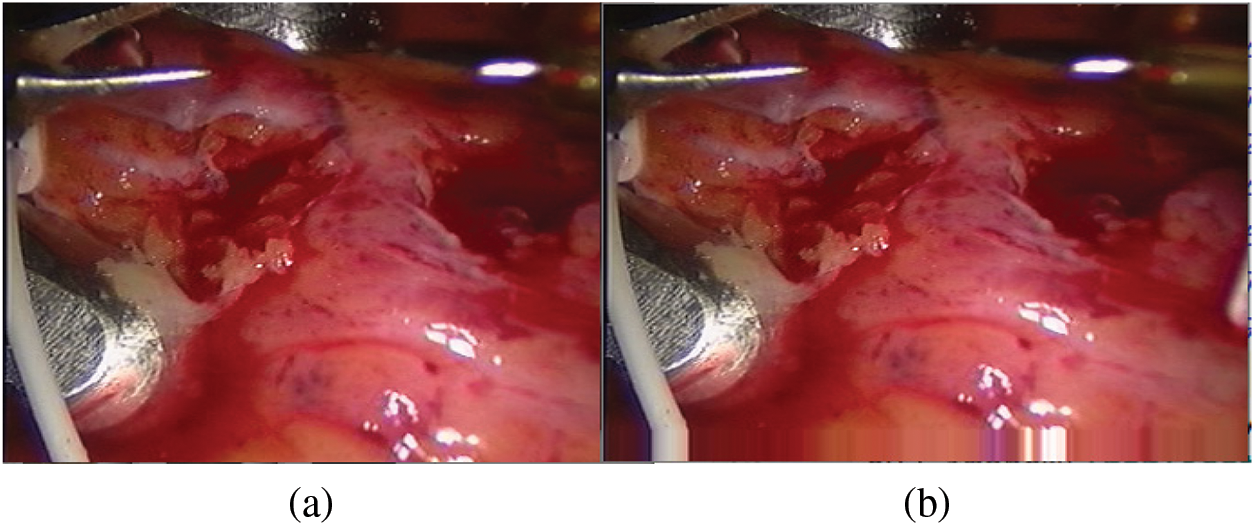

Medical dataset we used in this paper is a set of actual three-dimensional images of the soft tissue of the heart provided by Hamlyn Center at Imperial College London. They are available on the website: https://imperialcollegelondon.app.box.com/s/kits2r3uha3fn7zkoyuiikjm1gjnyle3.

The constructed matching data set is shown in Fig. 4. The first frame is our known frame, as shown in the figure, the 25th and 30th frames are the data sets matched by our triangle matching algorithm. Because the spot detection algorithm is affected by light, etc., the triangle matching can not match the first frame one by one, and there is spot loss in the subsequent frame

Figure 4: Screenshot and its spots (a) first frame (b) frame 25 (c) frame 30